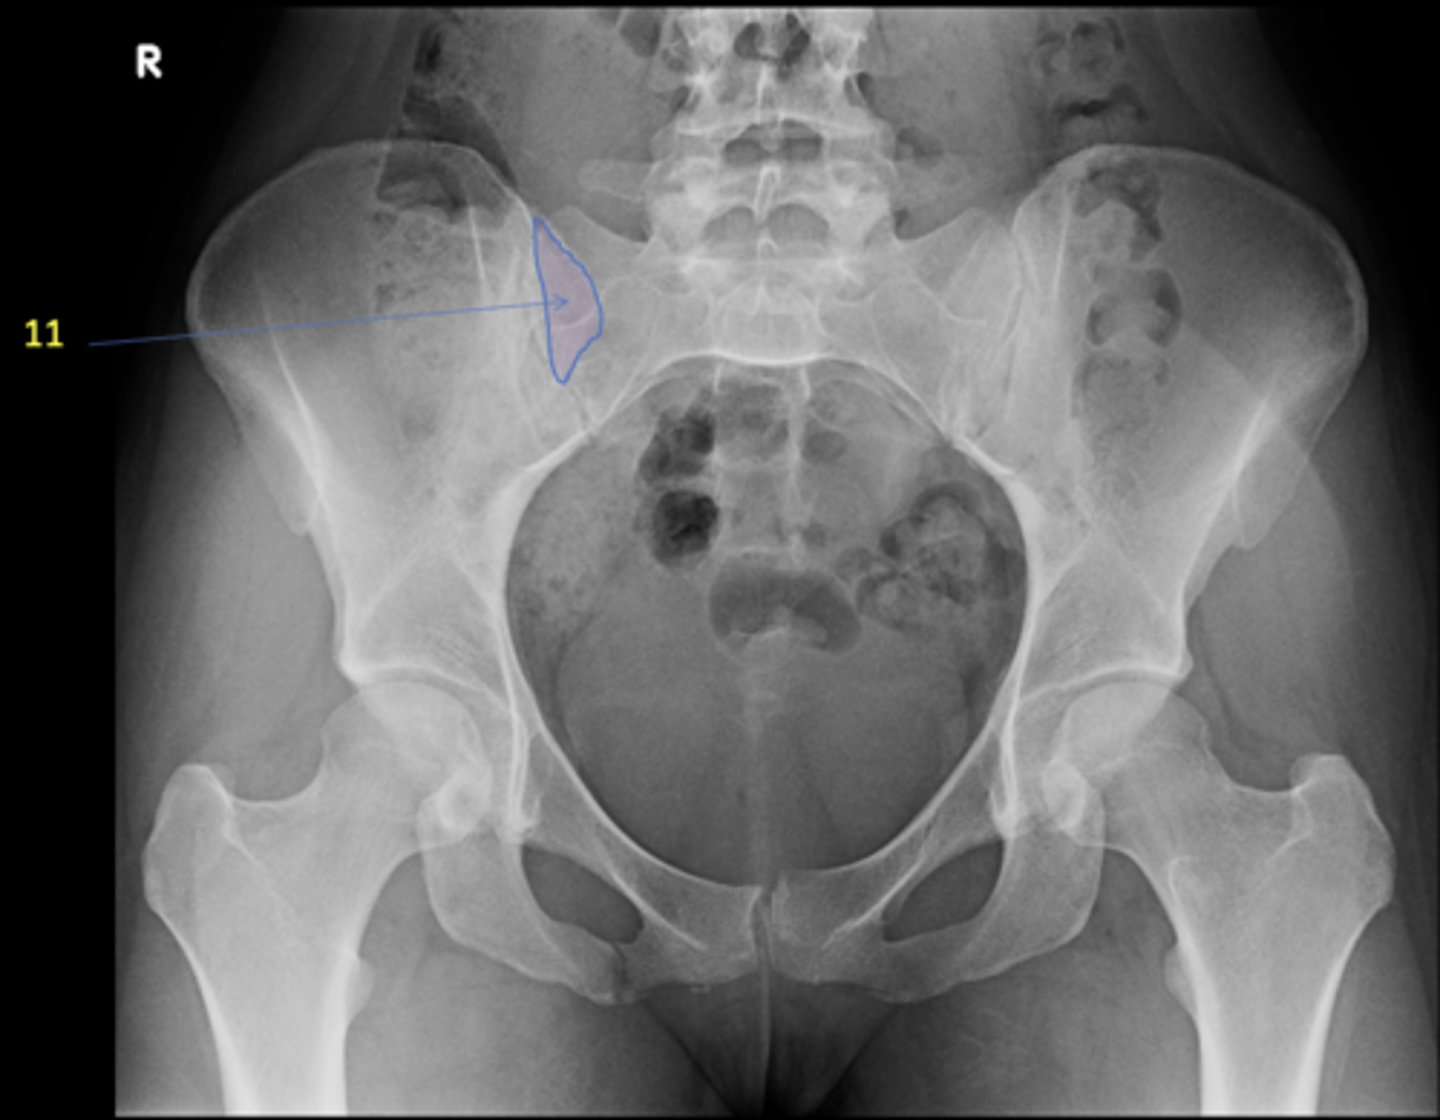

11

New cards

Right posterior superior iliac spine

ID 11

<p>ID 11</p>